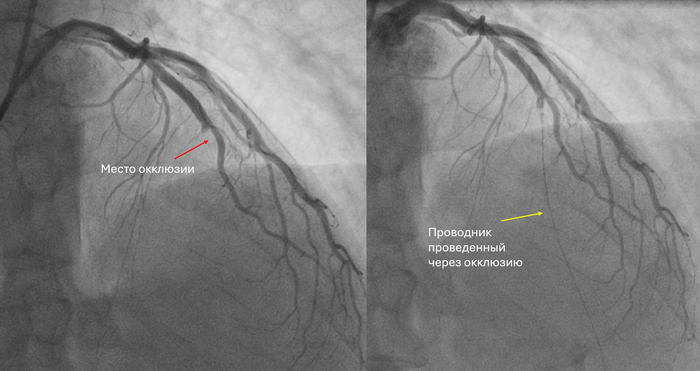

При терминальной стадии артроза голеностопного сустава (когда сустав тотально разрушен), есть два основных варианта хирургического лечения:

эндопротезирование (Эп, использую такие сокращения для простоты понимания) — ставят искусственный сустав, чтобы сохранить движение.

атродез (Ар) — сустав “выключают”: сращивают кости, движения в голеностопе больше нет, зато обычно уходит боль. Сразу обговорю: человек инвалидом не становится, он может ходить и даже заниматься спортом.

Слева артродезирование (то есть голеностопного сустава больше нет), а справа эндопротезирование (его заменили на искусственный).

Недавно вышло очень крупное исследование по Англии: взяли национальную базу операций с 1998 по 2023 год и сравнили, сколько людям потом требовалось повторных операций и какие были осложнения.

Сравнили результаты 10 335 эндопротезирований и 30 704 артродезирование.